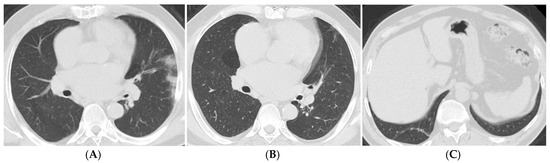

| Imaging Findings (3–6 Months) | Common Findings | Ground-glass opacities, parenchymal bands, traction bronchiectasis |